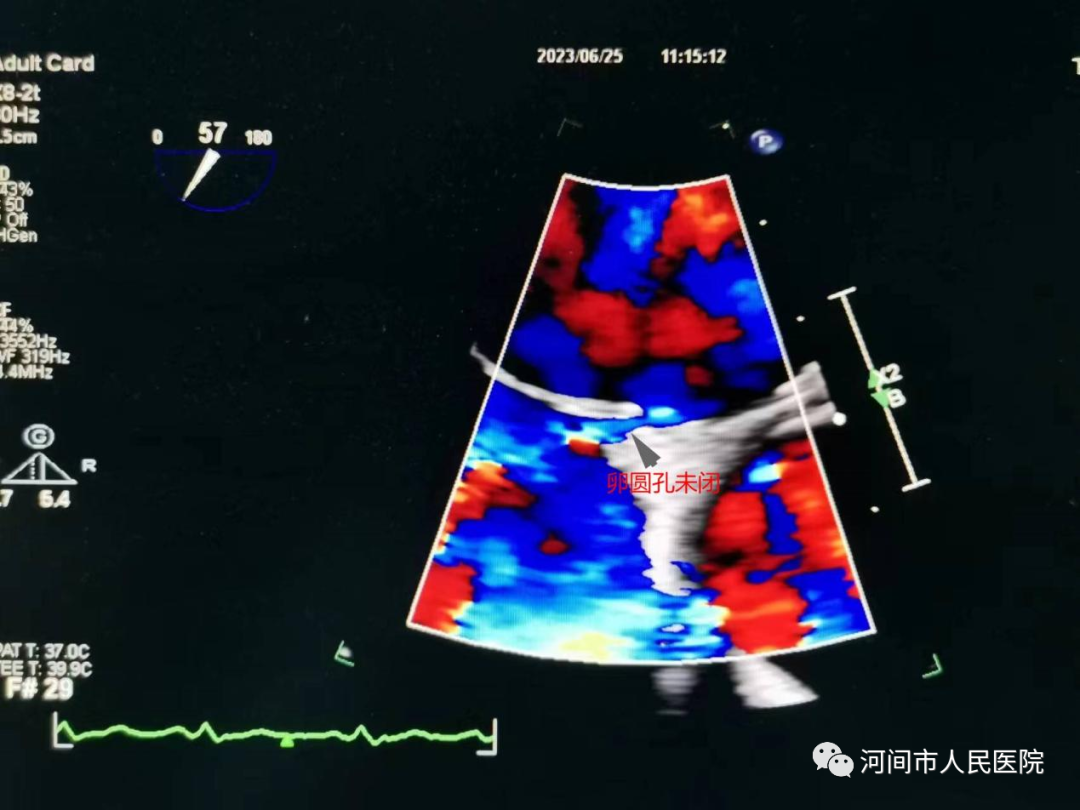

經食管超聲心動圖(TEE)是把超聲探頭放到食管內(nei) ,由於(yu) 探頭更貼近心髒,不像經胸超聲心動圖那樣受胸壁和肺氣影響,圖像顯示的更清晰,特別是對左心耳等經胸超聲不能看到的結構也能清晰顯示。

1、偏頭痛及年輕的腦卒中患者,懷疑有卵圓孔未閉的。